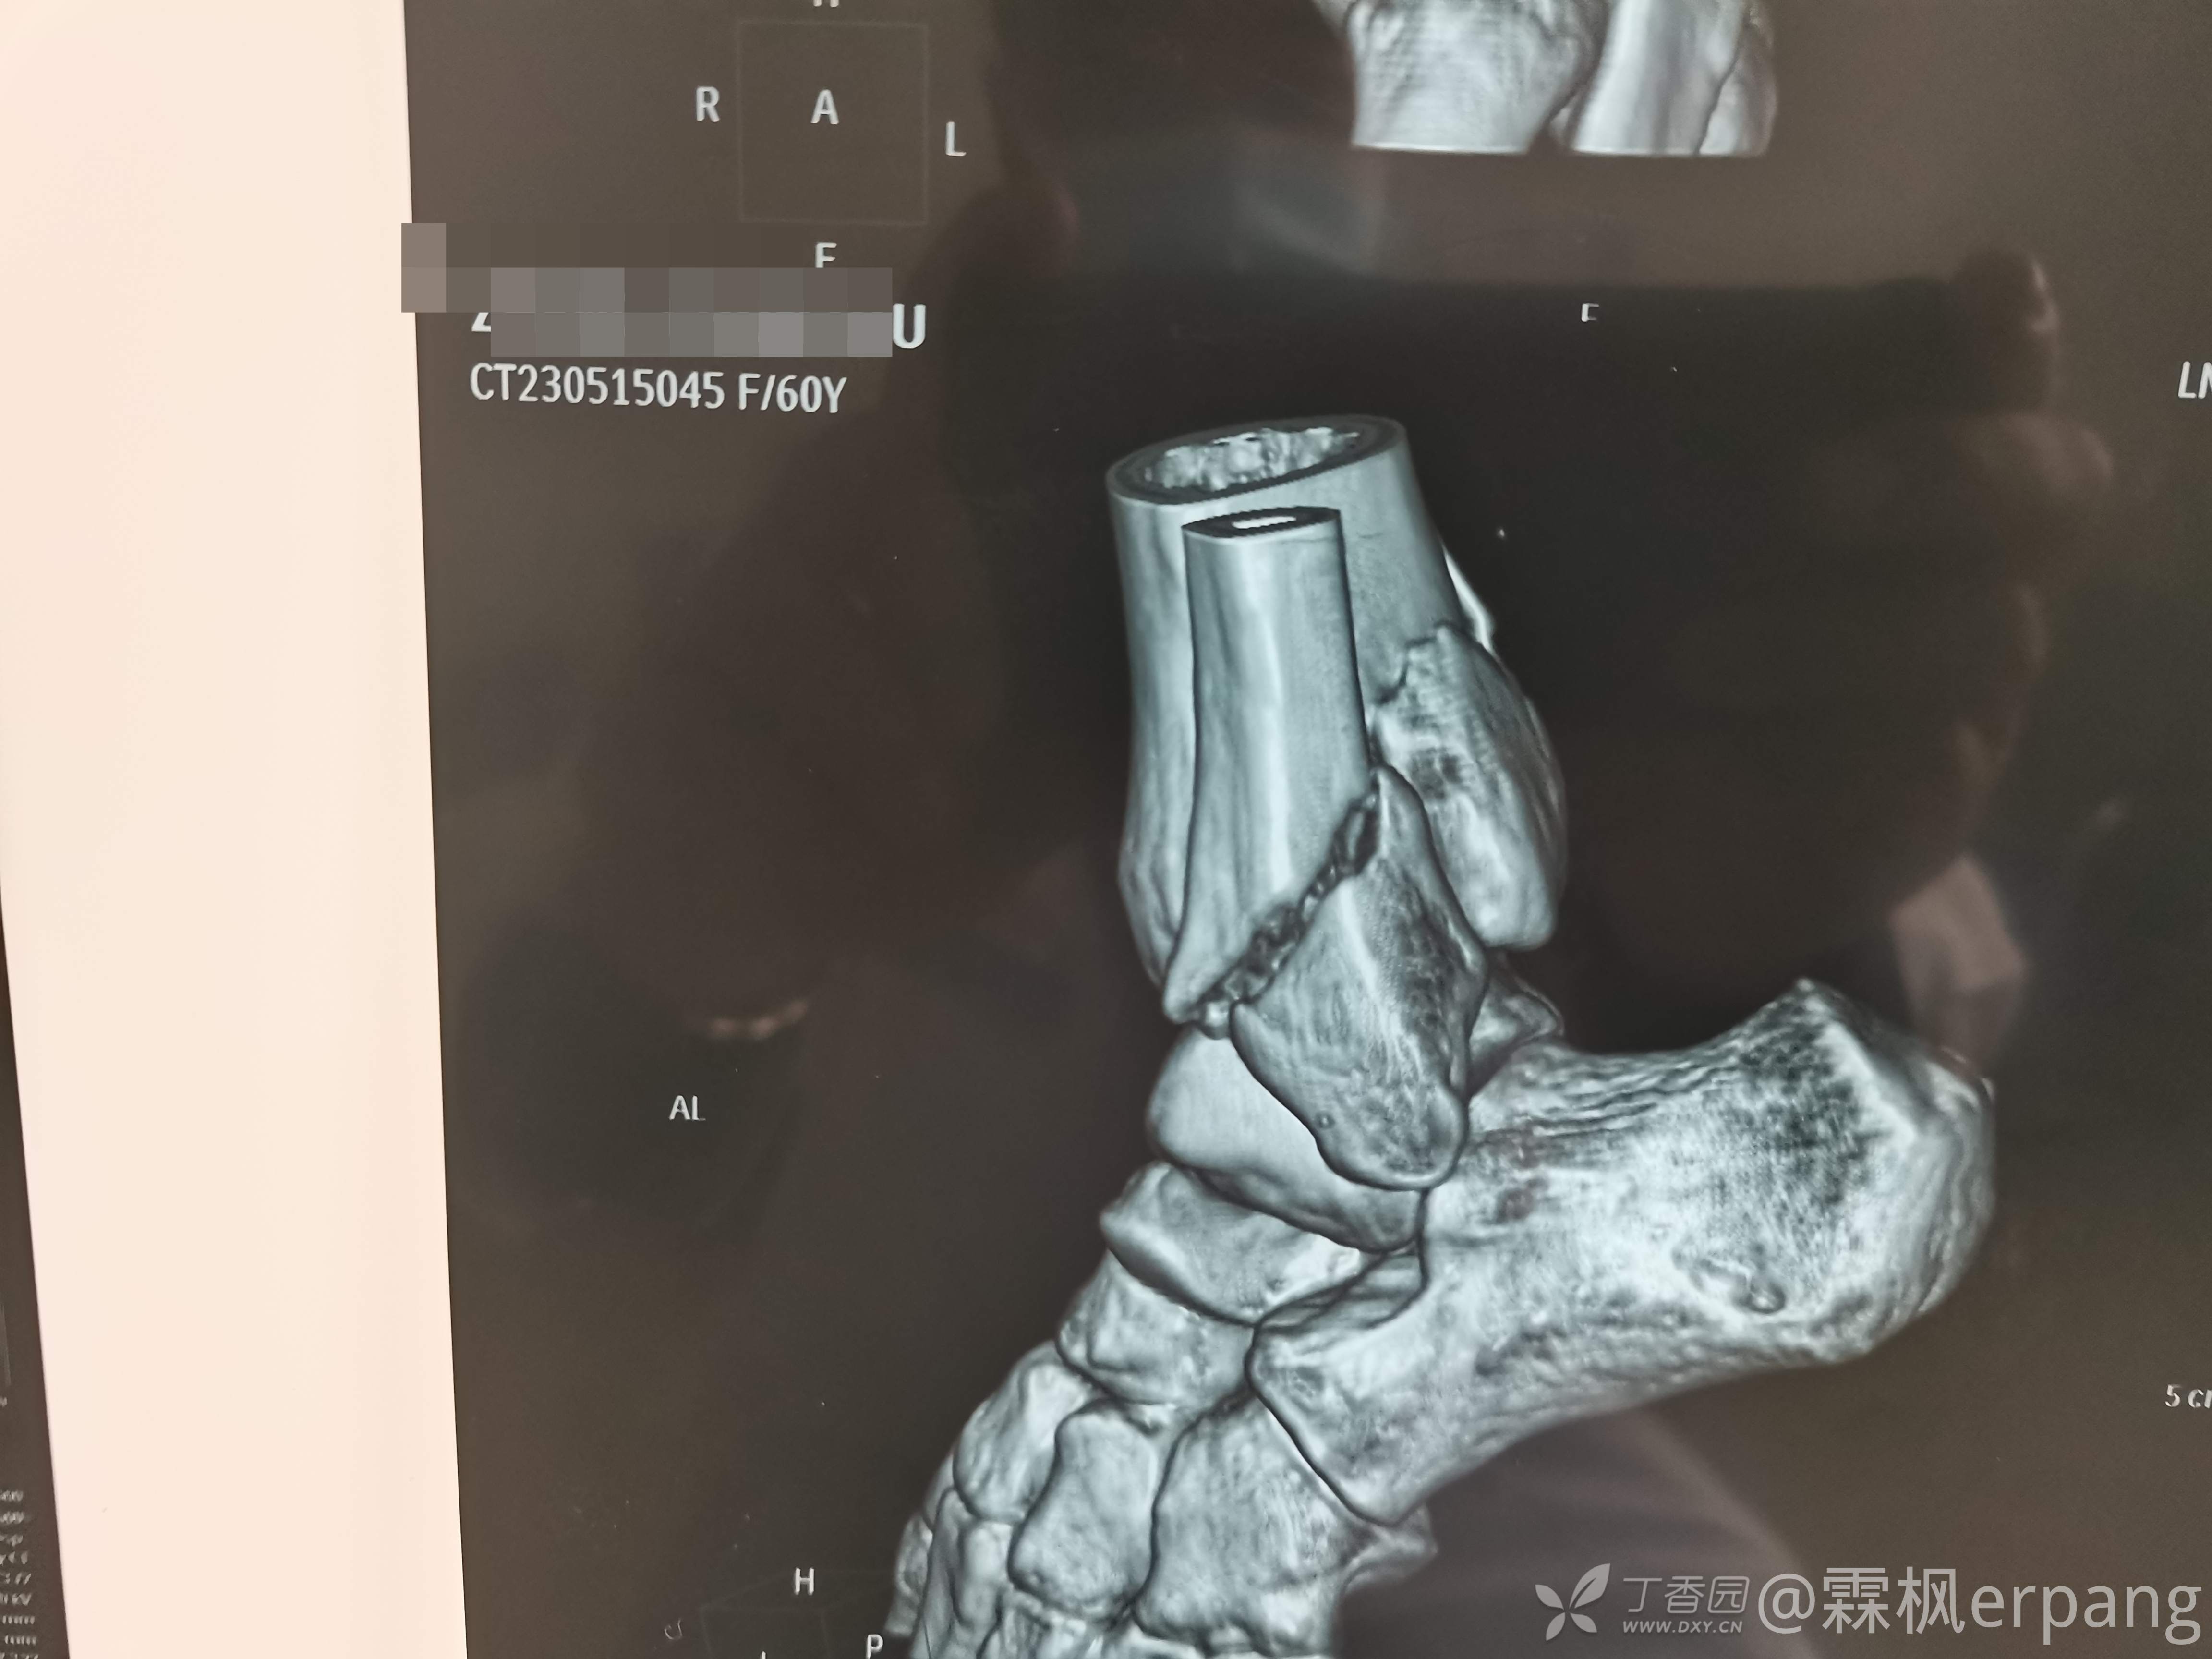

3度变4度

手术计划:后外侧切口做外踝和后踝,内侧闭合空心钉内固定。